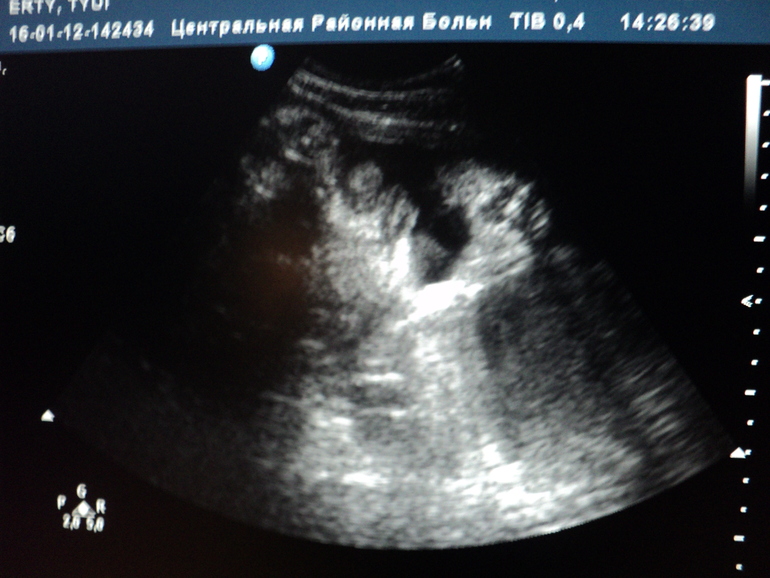

Сегодня были на УЗИ,врач сказала что по параметрам мы развиты на 36 недель,а срок всего лишь 33.Это ж ничего страшного?

Весит 2,214,меньше сладкого маме есть надо)

БПР 90

СДЖ 264

ДС 71

Лежим головкой вниз

Фото животика и с УЗИ